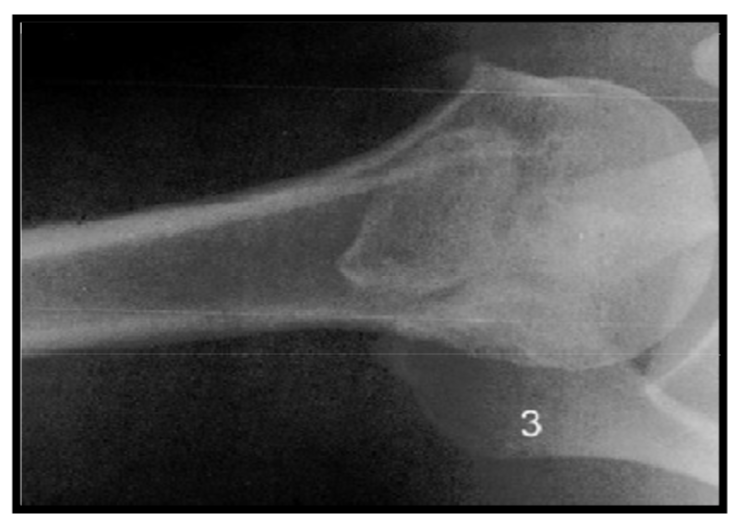

Synovial herniation pit or Pitt’s pit

variation anat normal